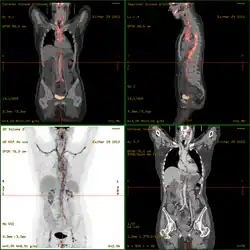

- 18F-fluorodeoxyglucose positron emission tomography/computed tomography (FDG-PET/CT)has become a widely used imaging tool in patients with suspected Large Vessel Vasculitis, due to the enhanced glucose metabolism of inflamed vessel walls.[41] The combined evaluation of the intensity and the extension of FDG vessel uptake at diagnosis can predict the clinical course of the disease, separating patients with favourable or complicated progress.[42]